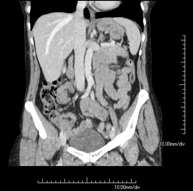

Prueba diagnóstica que consiste en obtener imágenes del abdomen de alta definición anatómica (hígado, vesícula biliar, vía biliar, páncreas, bazo, estómago, intestinos, riñones, estructuras vasculares, vejiga, útero y ovarios, etc.) mediante el empleo de un equipo de TC (Tomografía Computarizada). Dichas imágenes se estudian posteriormente en una estación de trabajo que permite reconstrucciones bidimensionales en diferentes planos del espacio, y también reconstrucciones 3D (volumétricas). La mayoría de estudios requieren el empleo de contraste yodado para mejorar la definición de las imágenes. - TC Pelvis

Prueba diagnóstica que consiste en obtener imágenes bi y tridimensionales del abdomen y de la pelvis de alta definición anatómica (estructuras óseas, estructuras vasculares, hígado, páncreas, vesícula biliar, riñones, glándulas suprarrenales, bazo, intestino delgado y grueso, vejiga, útero y ovarios, próstata y vesículas seminales, uréteres, etc.) mediante el empleo de un equipo de TC (Tomografía Computarizada). La mayoría de estudios requieren el empleo de contraste yodado. - TC Hígado